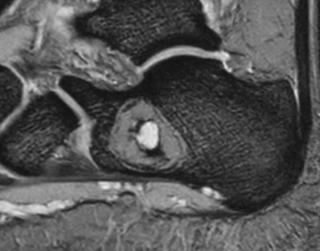

| MRI | 特徴的な**fluid–fluid level(液面形成像)**が多房性にみられる(出血層分離像)。T1で低〜中信号、T2で高信号。 |

| 造影MRI | 隔壁(中隔)の造影効果があり、血流豊富な壁構造を反映。 |